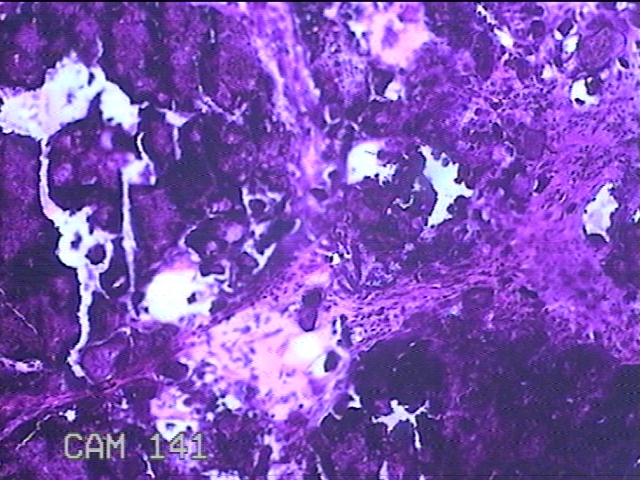

右侧臀部包块

性别

男

年龄

27岁

临床诊断

臀部良性肿瘤

一般病史

发现右侧臀部包块2年余,无明显疼痛及不适。

标本名称

大体所见

灰白暗红色组织2.3x1.7x1.3cm一块,表面带梭形皮肤2x1.3cm,皮下见包块2.3x1.3x1cm一个,切开包块呈实性,切面灰白粉红色,质中。

考虑瘤样钙质沉着,连蒙带猜了。